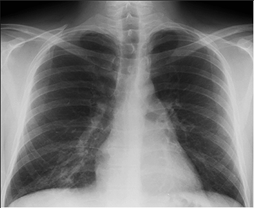

La

imagen de la izquierda corresponde a la radiografía de tórax de un paciente y

la de la derecha es una coloración de Gram a partir de una muestra de esputo de

ese paciente. Con base en las dos imágenes diga, ¿Cuál es el posible agente

causal del proceso neumónico?